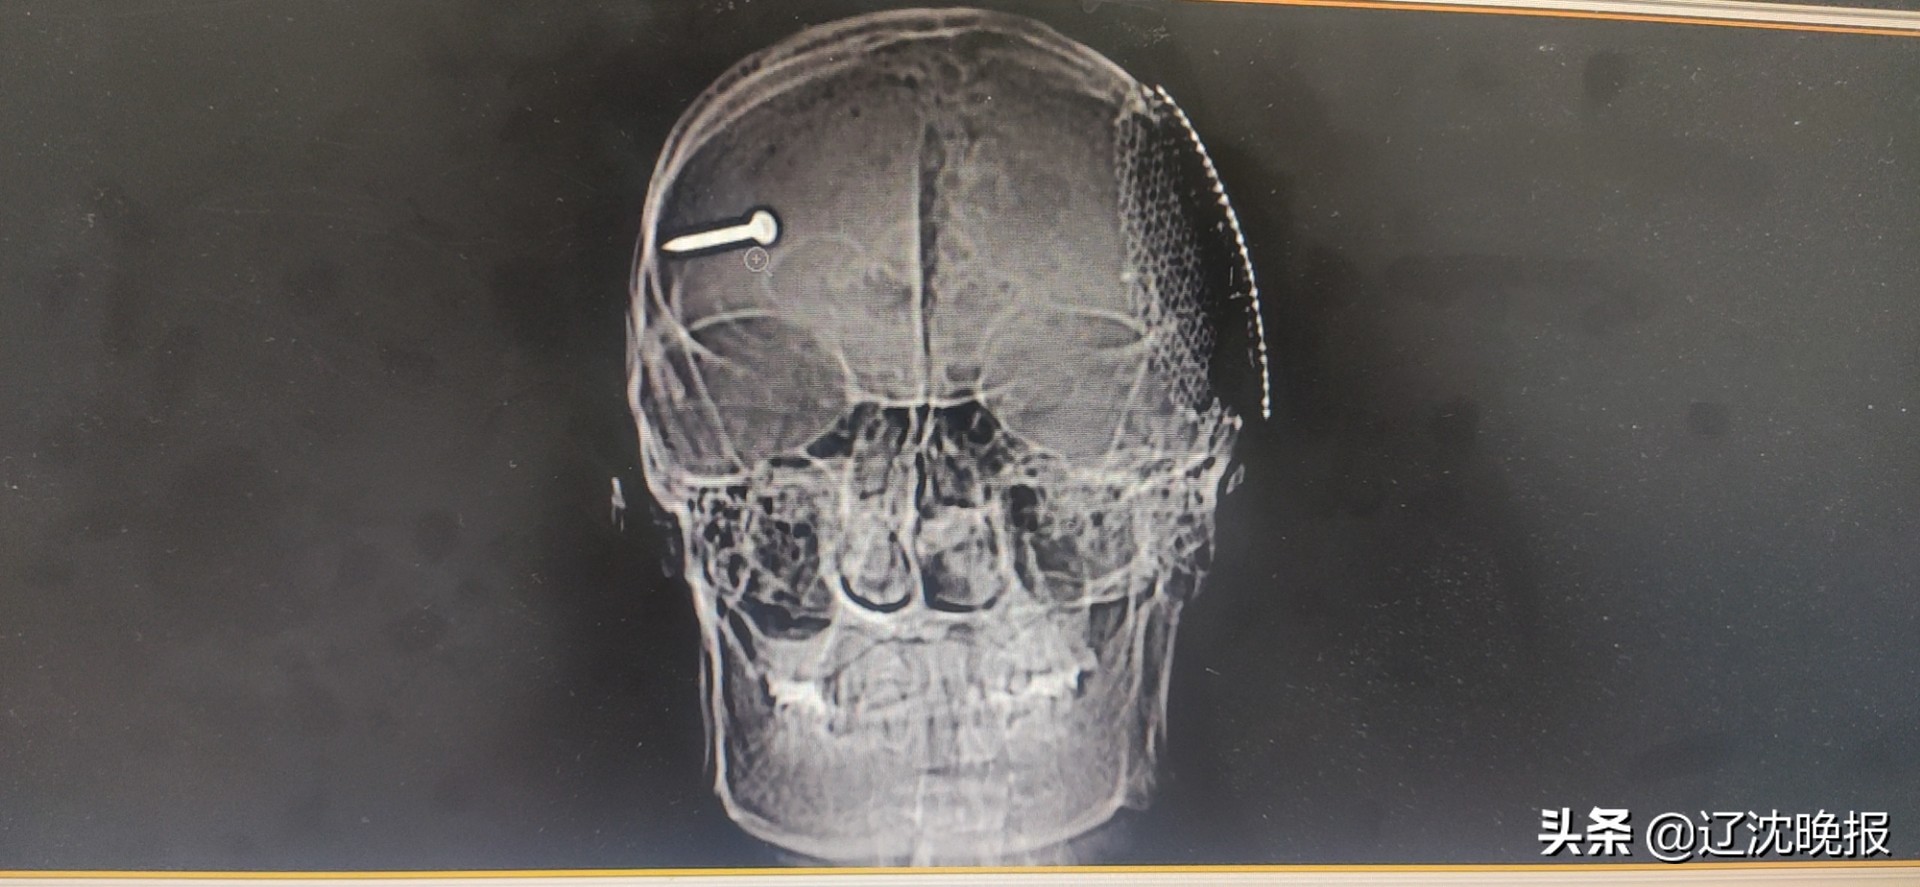

钢钉反弹伤人!一枚3.5厘米长的射钉枪钢钉,从工人眉心刺入,在大脑内穿行8.8厘米后,钉在头盖骨处。

患者脑部ct片子,钉子清晰可见。

医护人员首先对雷师傅进行清创、消毒,将开放伤转为闭合伤,随后处理双侧额颞皮瓣,显露眉心入口。李靖远告诉辽沈晚报记者:“钢钉从眉心正中间斜刺进入大脑,在穿过右侧大脑后被头盖骨拦住。”在眉心入口处以及钢钉停留处,医生还发现多片颅骨碎骨渣。“钢钉与碎骨渣都必须及时清除干净,否则可能引起颅内感染危及伤者生命。”

1分钟、2分钟、3分钟……整个手术过程持续225分钟!在显微镜下,李靖远使用双极镊子将钢钉与颅骨碎渣成功取出。“为避免伤者术后脑压过高等情况,我们用钛网替代修补颅骨缺口。”

在医生办公室,辽沈晚报记者看到被取出的钢钉与骨渣。经过现场测量计算,钢钉长度达3.5厘米,颅骨碎渣多达9片。有术前资料显示,钢钉在刺入大脑后继续穿行8.8厘米,才被头盖骨截停。伤者并不是第一次受到大脑损伤,在大约十年前,雷师傅也曾经因为类似颅脑受伤,接受开颅手术。